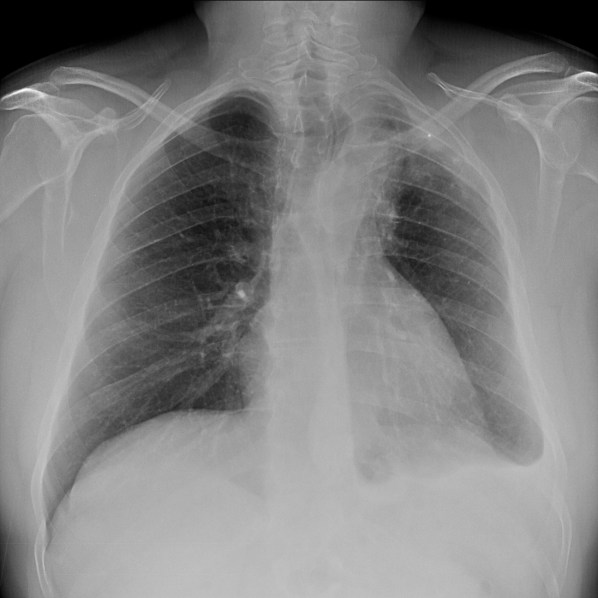

Mismo paciente, al cual esta vez se le ha tomado una radiografía en PA y en sedestación. Observar como las clavículas están equidistantes a las apófisis espinosas y como ha desaparecido el velamiento del pulmón izquierdo.

Por otra parte, paciente presenta una cardiomegalia y un discreto ensanchamiento del mediastino es probable relación con cambios postquirúrgicos.